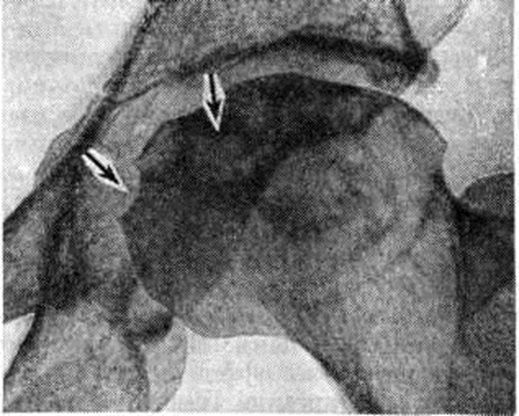

Рис. 4.

Рентгенограмма правого тазобедренного сустава больного с хронической: почечной недостаточностью (асептический некроз головки бедренной кости): головка бедренной кости деформирована; стрелками указаны участки остеонекроза кости.